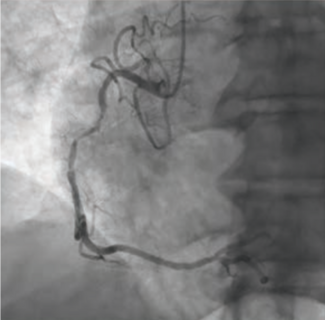

The authors share a case of a large LAD-to-right-sided coronary cameral fistula that produced angiographic coronary steal but no significant shunt, allowing for successful conservative management.